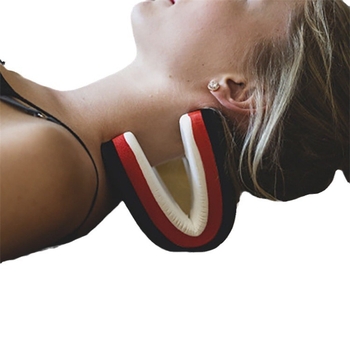

A Badu nem vállal felelősséget a vásárlásért Nyaktartó masszázspárna húzási és ortozissal – XMG modell 445345, polietilén anyag, doboz 60, egészségügyi masszázs Ettől: Egészségügyi Eszközök Kiegészítői Ha az nem a megrendelőlapon keresztül történt.